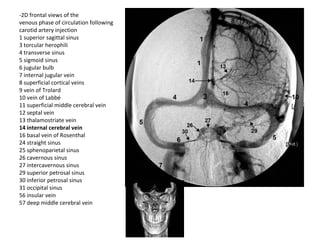

-2D frontal views of the venous phase

of circulation following vertebral

artery injection

1 superior sagittal sinus

3 torcular herophili

4 transverse sinus

5 sigmoid sinus

6 jugular bulb

7 internal jugular vein

26 cavernous sinus

27 intercavernous sinus

29 superior petrosal sinus

30 inferior petrosal sinus

35 anterior pontomesencephalic vein

37 posterior mesencephalic vein

39 petrosal vein

41 precentral cerebellar vein

43 inferior vermian vein

44 cerebellar hemispheric vein

45 brachial vein

46 suboccipital veins

49 parietal veins

-2D frontal views of the

venous phase of circulation following

carotid artery injection

8 superficial cortical veins

9 vein of Trolard

10 vein of Labbé

11 superficial middle cerebral vein

12 septal vein

13 thalamostriate vein

14 internal cerebral vein

16 basal vein of Rosenthal

24 straight sinus

25 sphenoparietal sinus

31 occipital sinus

56 insular vein

57 deep middle cerebral vein